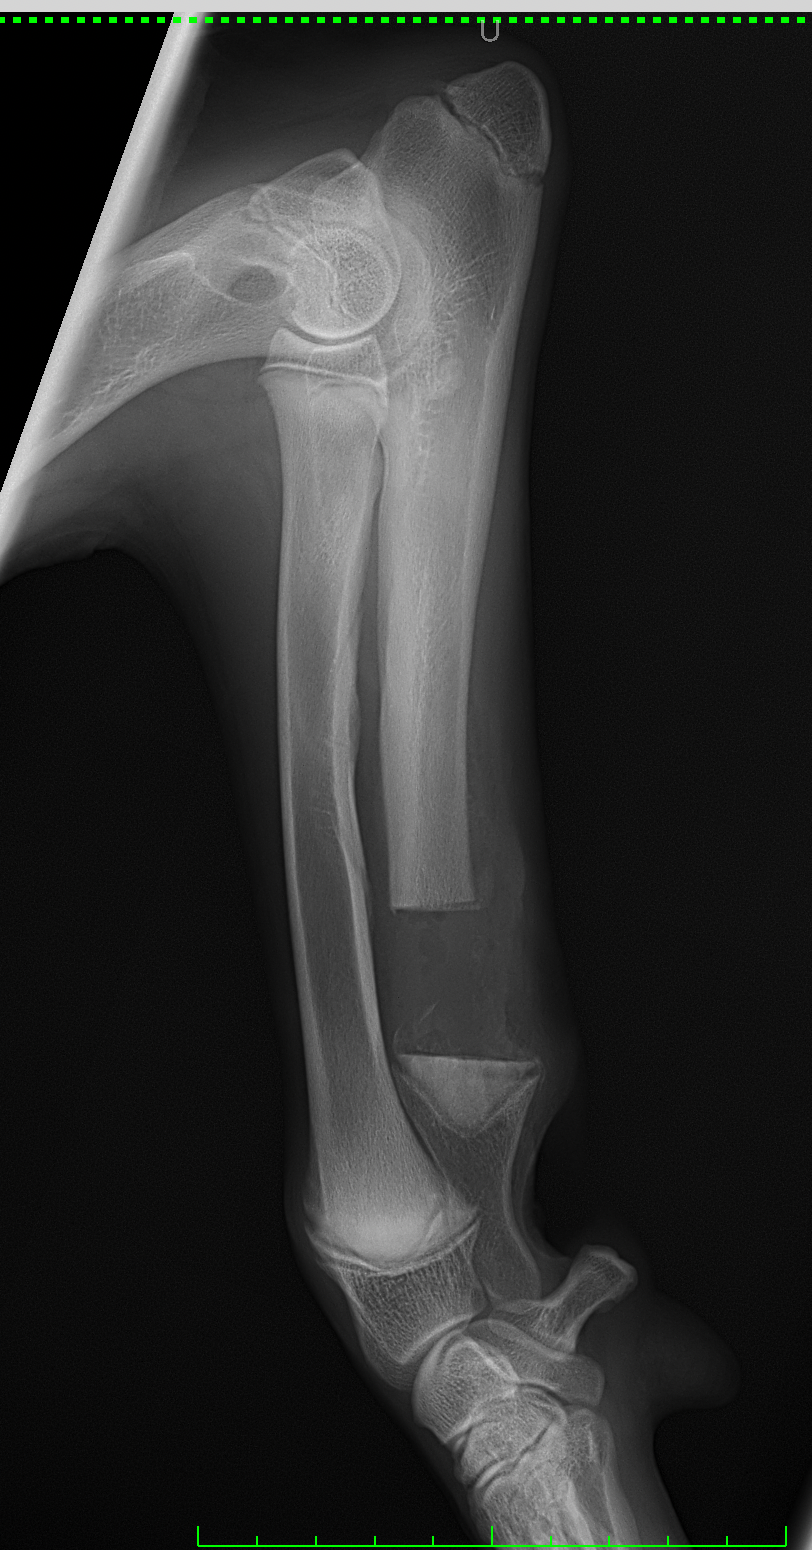

遠位尺骨部分切除術 大型犬のパピー(5mo)の前腕変形に対して、尺骨遠位骨部分切除術を実施。橈骨の成長が終了するまで待ってから変形による有痛症状があれば関節鏡による探査と橈骨の変形矯正を検討します。 症例カテゴリー 放射線治療整形外科軟部組織外科脳神経外科内科腫瘍外科救急・集中治療リハビリテーション科腫瘍内科内視鏡科脳神経科呼吸器外科中医・漢方猫の腎移植循環器科